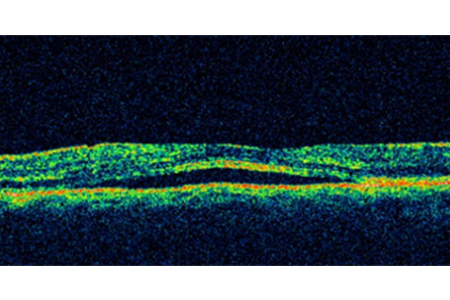

Normal OCT